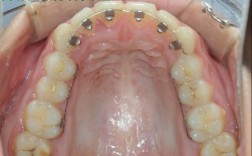

- 牙冠:即暴露在口腔中、模拟自然牙形态的部分,由全瓷、烤瓷或金属烤瓷等材料制成,可根据邻牙颜色、形状定制,达到以假乱真的美观效果,患者日常看到的“牙齿”,实际是牙冠,而非种植体本身。

- 口腔清洁:使用软毛牙刷、冲牙器或专用种植牙刷清洁牙冠与牙龈交界处,避免食物嵌积引发牙龈炎,若牙龈红肿萎缩,可能导致基台或种植体边缘暴露。